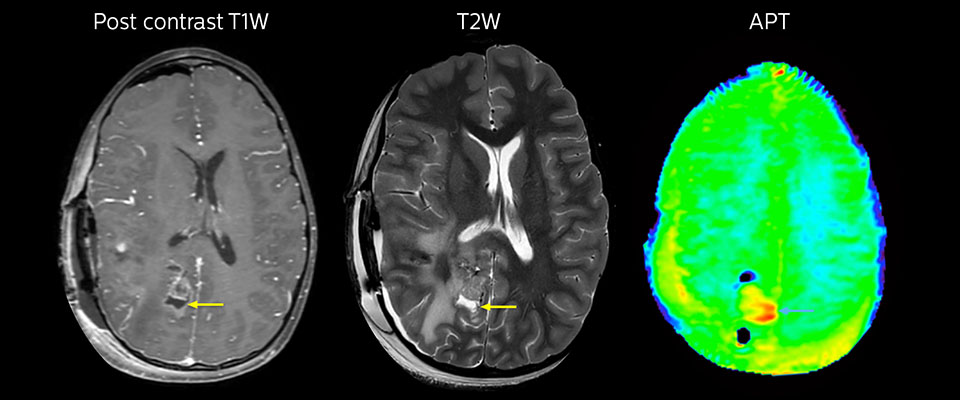

APT imaging of high-grade tumor

Tumor evaluation in a 1-year-old child with medulloblastoma. This aggressive tumor type is very solid and homogeneous. The high APT signal corresponds with the post-contrast image of this high-grade tumor.

APT may be a powerful addition to grade tumors with MRI